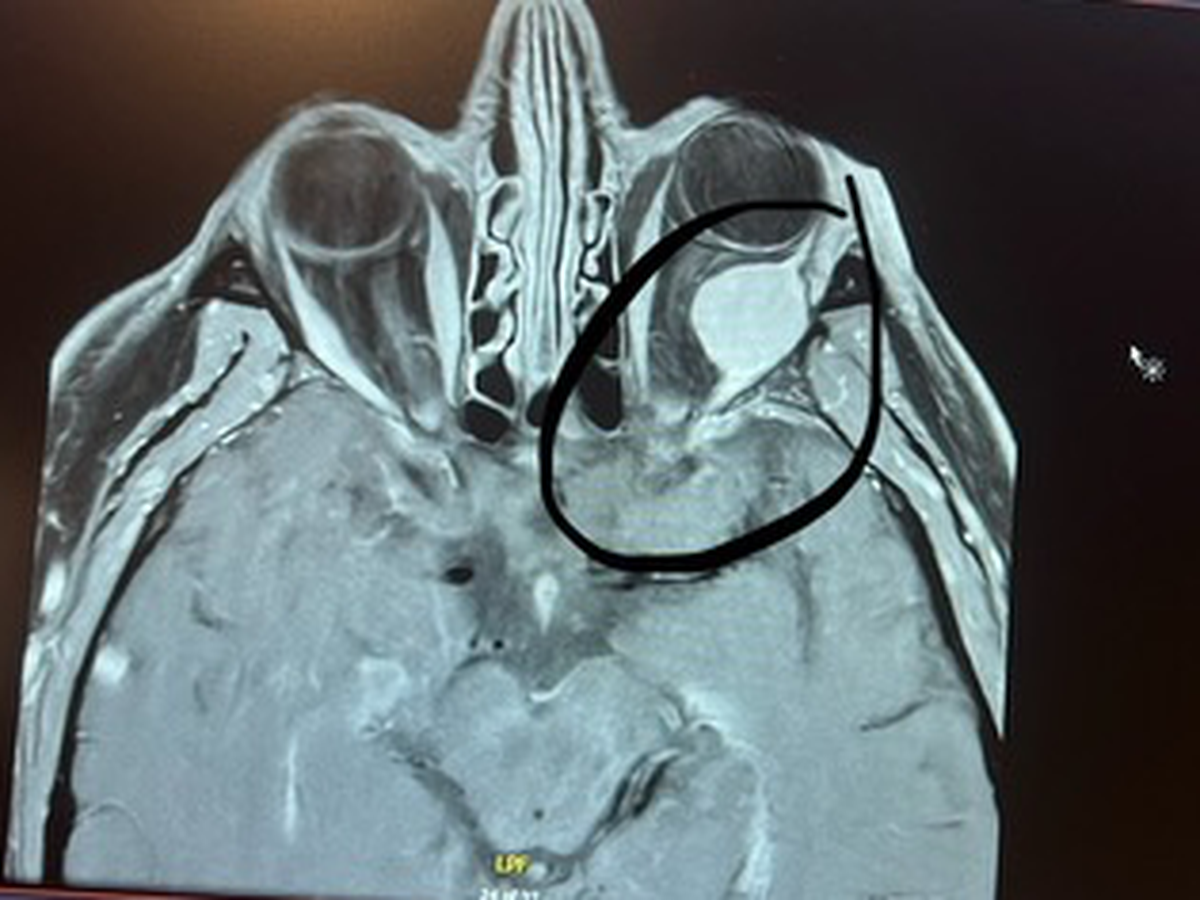

In December my dad started experiencing eye pain that was treated with eye drops but didn’t get better. On Monday, January 20th he went for a second opinion and a CT scan of his sinuses revealed a large mass behind his eye and the following day was confirmed by MRI. Things escalated pretty quickly from here as the mass was touching the optic nerve. He was quickly referred to Augusta for immediate evaluation. Here he met with an Oculoplastic surgeon who completed an exploratory surgery and biopsy on January 31st. Sadly on February 4th he was hit with a brutal diagnosis of Metastatic Melanoma. Since that day he’s completed an MRI Brain and a PET scan which showed 2 additional spots in the brain and multiple nodules in both lungs. This led to an official diagnosis by his oncologist of Stage 4 Metastatic Melanoma, which is devastatingly incurable.